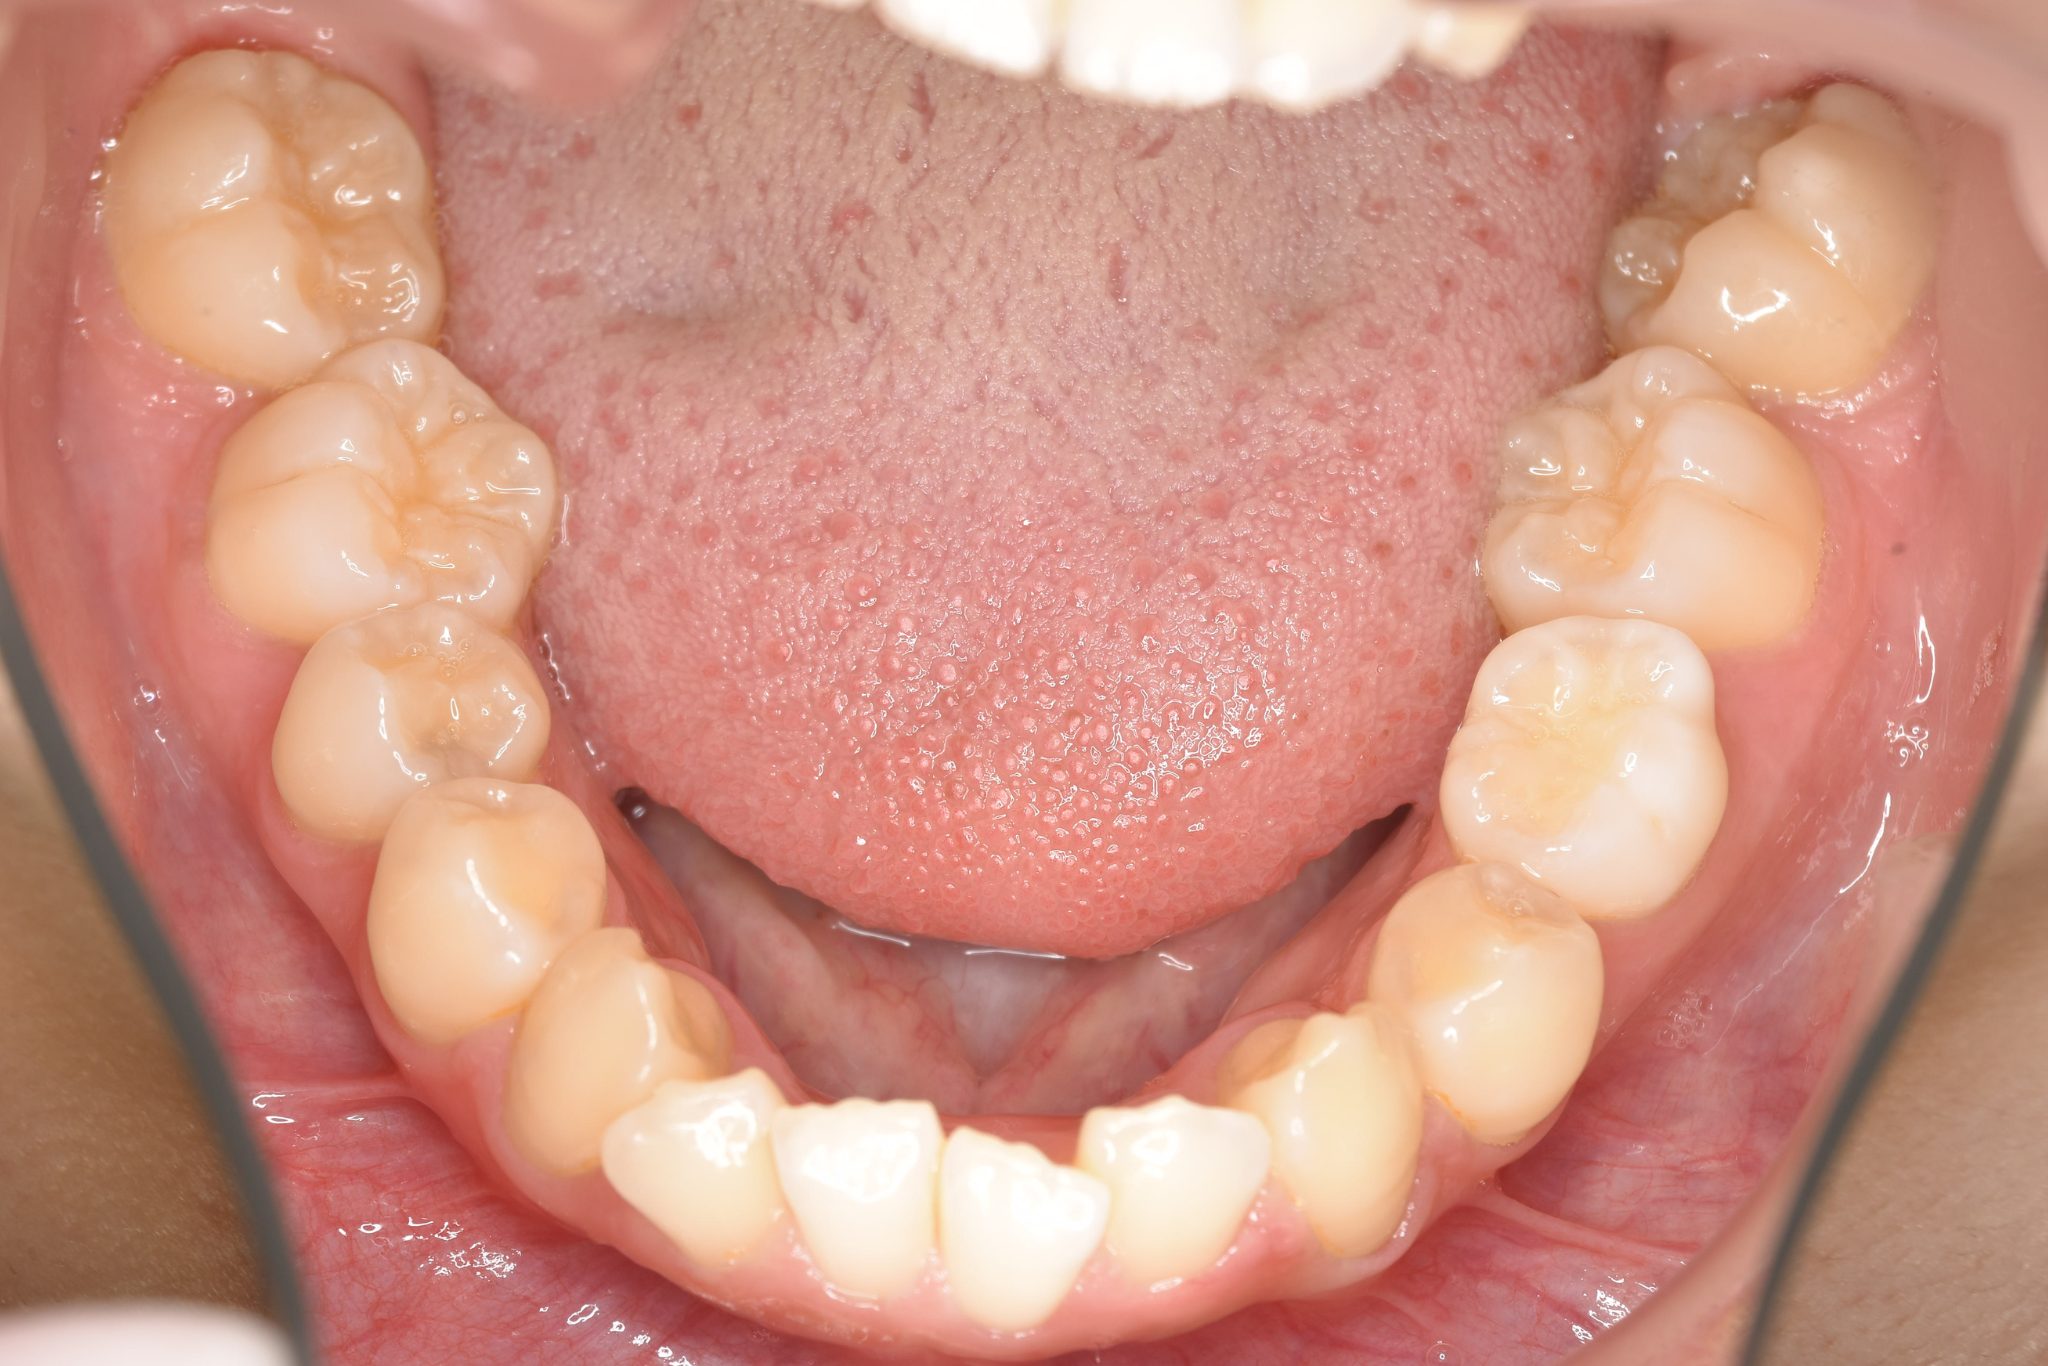

ビフォー

全顎ワイヤー矯正 症例_418

主訴 歯並びがガタガタ ※抜歯あり

施術内容 成人矯正1期治療

治癒期間 2年10か月間

費用 1,069,200円(税込)